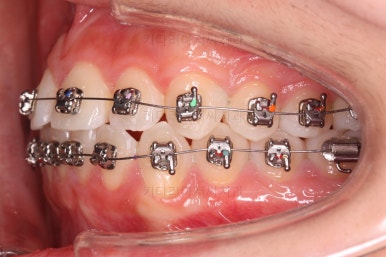

쓰러져 있던 치아도 장치를 부착하여 일으켜 세워주는 힘을 줍니다.

자칫 나머지 치열이 틀어질 수 있기 때문에 아랫니에는 미니스크류를 이용해서 반작용을 막아줍니다.

점점 뒤쪽 치아가 바로 일으켜 세워지고 있네요.